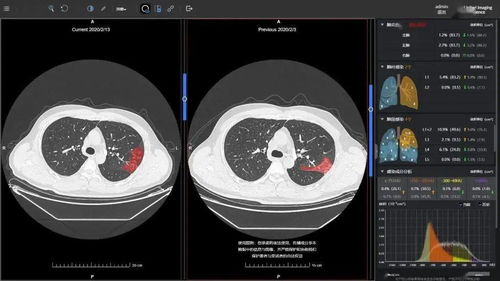

3. AI辅助诊断

人工智能技术在CT医学影像系统中的应用,可以提高诊断效率和准确性,降低误诊率。